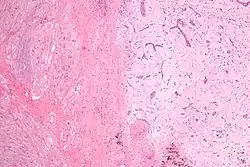

Синдро́м Ка́рнея (ко́мплекс Ка́рни, синдром Карни) — редкое наследственное заболевание с аутосомно-доминантным типом наследования. Характеризуется образованием у детей множественных опухолей (миксомы сердца, пигментные опухоли кожи, пигментная узловая гиперплазия надпочечников, фиброаденомы молочных желез, опухоли яичек, СТГ-секретирующие аденомы гипофиза)[1][2][3]. Следует отличать от триады Карни[4].

Симптомы зависят от размера, подвижности и расположения опухоли. Пятнистая пигментация кожи чаще всего встречается на лице, особенно на губах, веках, конъюнктиве и слизистой оболочке полости рта[2]. Миксома сердца может привести к тромбоэмболии, сердечной недостаточности[6] и может проявляться лихорадкой, болью в суставах, одышкой, диастолическим шумом. Миксома может развиться вне сердца, как правило, на коже и в груди. Клинически эндокринные опухоли могут проявляться в виде расстройств, характерных для синдрома Кушинга.